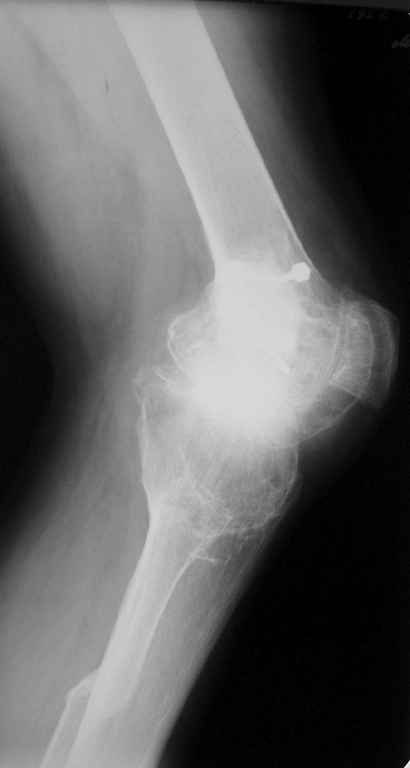

Пациент 59 лет, в 1982 году по поводу остеобластокластомы была выполнена частичная резекция проксимального отдела бедра с пластикой дефекта костно-хрящевым трансплантатом (моноблок)с фиксацией металлическими стяжками.

В последующем по поводу деформирующего артроза выполнена корригирущая остеотомия большеберцовой кости. Исход представлен на рентгенограмме. В настоящий момент пациента беспокоят боли  в коленном суставе, деформация, и ограничение движений. Варусная деформация коленного сустава 20, движения сгибание 115, разгибание 150, ходит с тростью, выраженная хромота, работа не связана с физическими нагрузками. Правый коленный сустав без патологии. Уважаемые коллеги просим высказать своё мнение - артродез  коленного сустава или эндопротезирование.